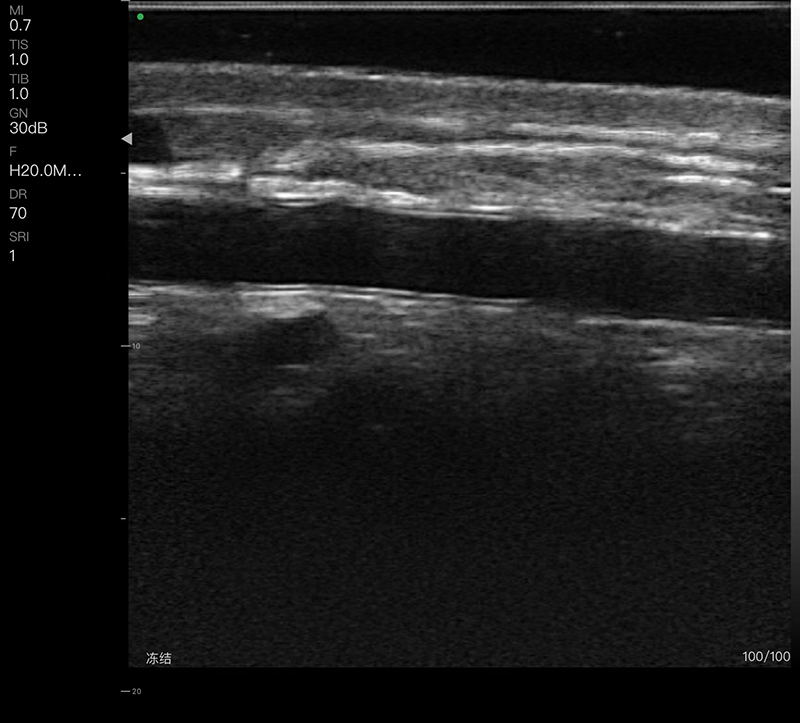

• 探头频率:线阵7.5/10MHz,高频线阵16/20MHz

• 扫描深度:20/40/60/80mm可调

• 扫描宽度:线阵40mm,高频线阵25mm